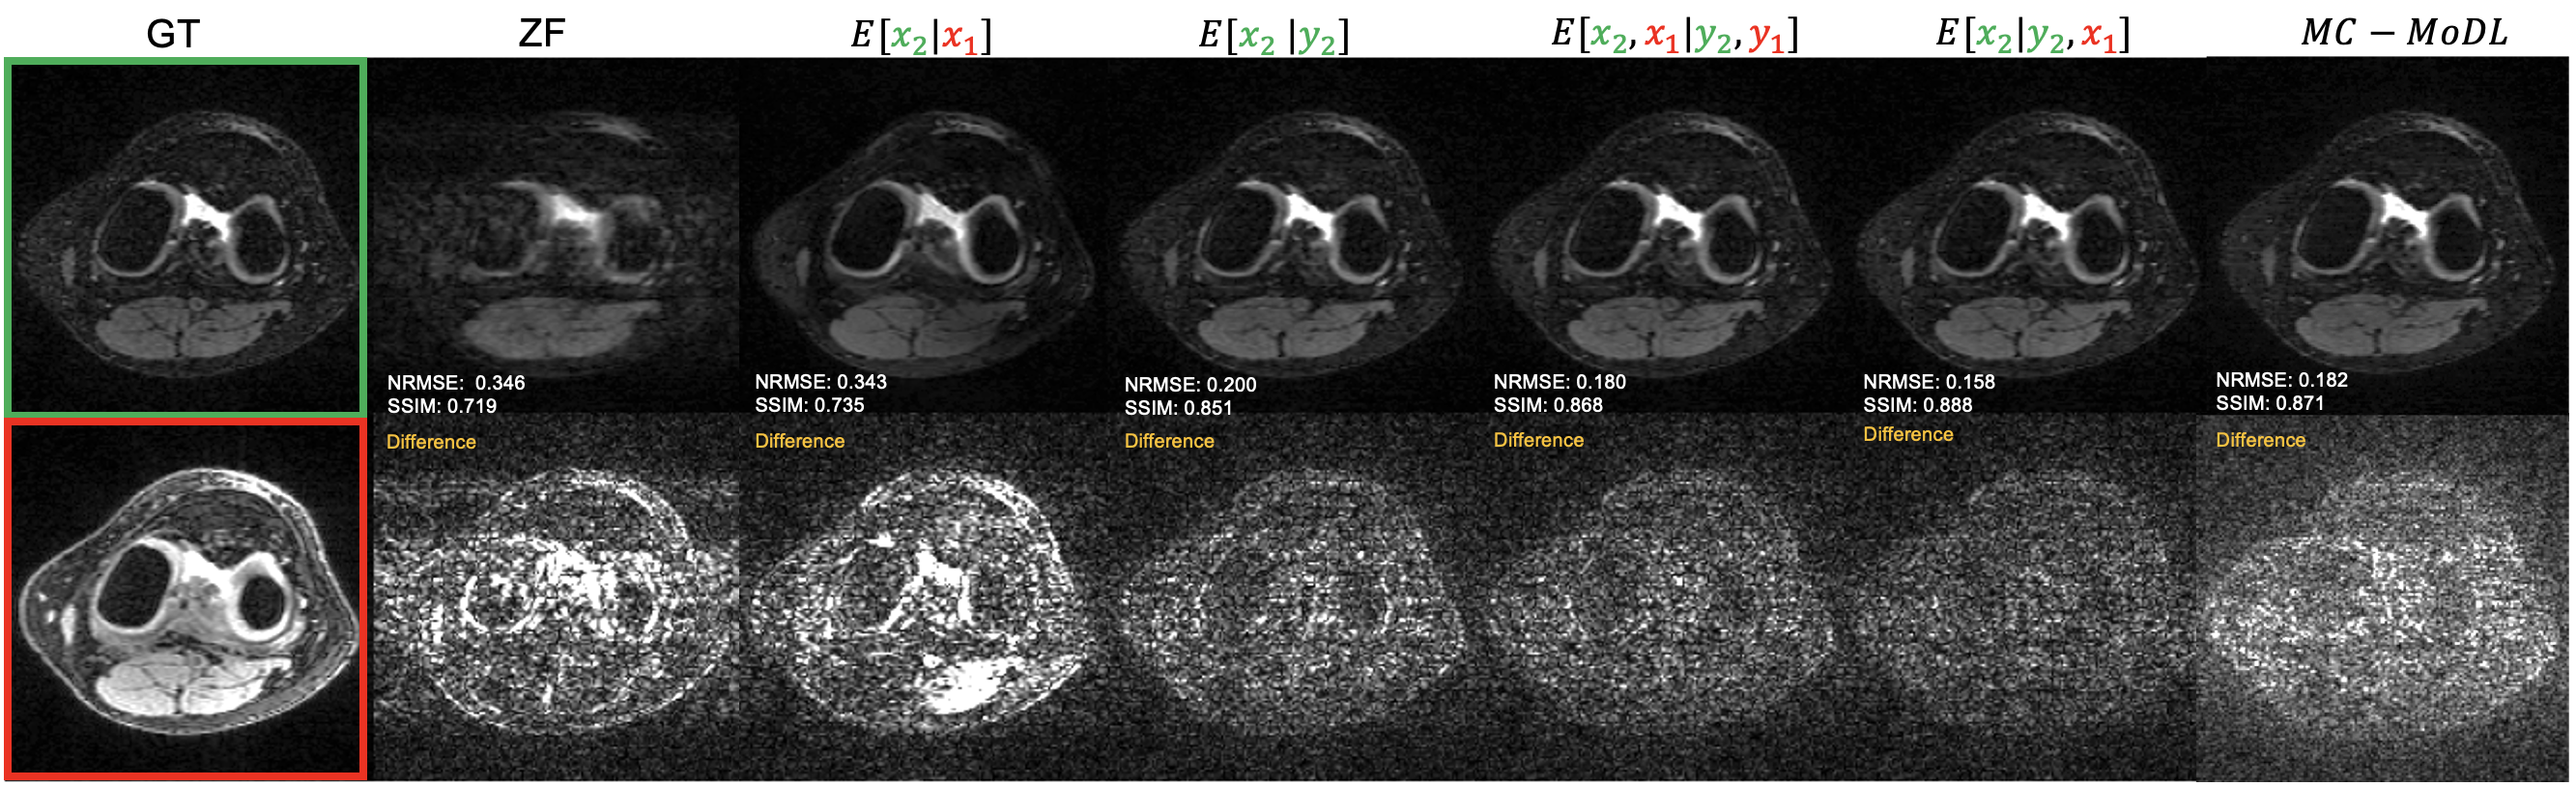

In the joint reconstruction scenario, we sampled both x1subscript𝑥1x_{1} and x2subscript𝑥2x_{2} at the prescribed acceleration level by collecting the same 121212 ACS lines and independent uniform random sampling for the remaining phase encode (PE) lines in each image contrast (Fig. 2). For the prior image conditioned reconstruction we only took under-sampled measurements from the target contrast x2subscript𝑥2x_{2} by, again, collecting an ACS region and uniform random sampling for the remaining PE lines (Fig. 2). The test set included 100100100 slices from three volumes (300300300 slices in total) not seen in the training or validation datasets. For each test image we conducted five different reconstructions: (1) Zero-filled IFFT (ZF), (2) Sample x2subscript𝑥2x_{2} given only the fully sampled prior image x1subscript𝑥1x_{1} (E[x2|x1]𝐸delimited-[]conditionalsubscript𝑥2subscript𝑥1E[x_{2}|x_{1}]), (3) Sample x2subscript𝑥2x_{2} using only its own under-sampled measurements y2subscript𝑦2y_{2} (E[x2|y2]𝐸delimited-[]conditionalsubscript𝑥2subscript𝑦2E[x_{2}|y_{2}]), (4) Sample x2subscript𝑥2x_{2} from under-sampled measurements of both contrasts (E[x1,x2|y1,y2]𝐸subscript𝑥1conditionalsubscript𝑥2subscript𝑦1subscript𝑦2E[x_{1},x_{2}|y_{1},y_{2}]), (5) Sample x2subscript𝑥2x_{2} from under-sampled measurements y2subscript𝑦2y_{2} and fully sampled prior image x1subscript𝑥1x_{1} (E[x2|y2,x1]𝐸delimited-[]conditionalsubscript𝑥2subscript𝑦2subscript𝑥1E[x_{2}|y_{2},x_{1}]). In each case we averaged 101010 posterior samples for the reconstruction. The step size ηtsubscript𝜂𝑡\eta_{t} was tuned individually for each method using a single validation patient with 100100100 samples at R=4𝑅4R=4.

Numerical results for reconstructing x2subscript𝑥2x_{2} in the joint reconstruction case are shown in Table I for each approach described above. Example reconstructions for R=3𝑅3R=3 are shown in Fig. 5. The top and bottom images in the left most column are x2GTsuperscriptsubscript𝑥2𝐺𝑇x_{2}^{GT} and x1GTsuperscriptsubscript𝑥1𝐺𝑇x_{1}^{GT} respectively. The remaining columns each represent a different reconstruction technique as described in Section III-C. For each reconstruction technique the top row is the reconstructed image and the bottom row contains the difference image between the reconstructed image and the ground truth image. All images are plotted on the same dynamic range and the difference images are scaled by a factor of 101010. Table II shows the reconstruction metrics for when we apply the joint reconstruction techniques to data that has been sampled with a different pattern at R=3𝑅3R=3. Figure 6 shows an example reconstruction for this case. Results for the prior guided image reconstruction experiment where we have access to a fully sampled prior image x1GTsuperscriptsubscript𝑥1𝐺𝑇x_{1}^{GT} are shown in Table III.

Refer to caption

Figure 5: Reconstruction of a slice from the test set at R=3𝑅3R=3 with vertical sampling. Left-most column shows the ground-truth (GT) x2subscript𝑥2x_{2} and x1subscript𝑥1x_{1}. Top: reconstruction of x2subscript𝑥2x_{2} given different side information. Bottom: Difference image with ground-truth.